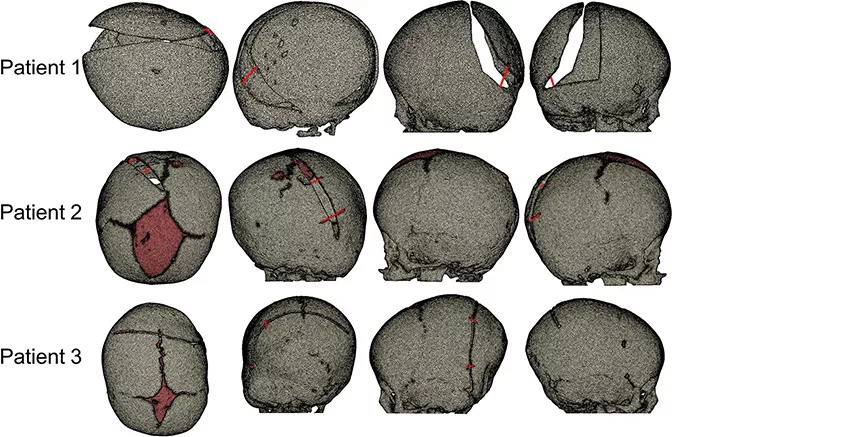

为模拟划分网格

在 Simpleware FE 中采用结构化的 3D 四面体单元生成颅骨的有限元(FE)模型,对不同的解剖区域赋予合适的材料属性建模。在对颅骨模型进行截骨之前,通过使用热膨胀系数在 MSC Marc 中近似模拟术前成像和手术之间的颅骨生长。将颅内体积(ICV)作为表示不同阶段颅骨大小的参数,包括在 Simpleware ScanIP 中通过选择颅顶内表面进行术前CT重建。

通过在 Simpleware ScanIP 中追踪手术保留的可见痕迹估算术中 ICV,以此复制手术时的颅骨截骨。然后重新划分截骨的颅骨结构,使用 MSC Marc 中的弹簧/阻尼器连接元件模拟弹簧植入,展示手术和术后 CT 扫描的差异。